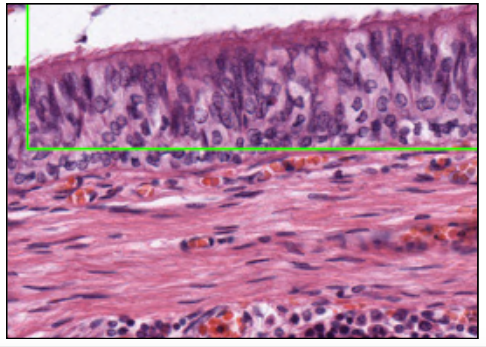

RESPIRATORY EPITHELIUM (TOLUIDINE BLUE)

SIMPLE/PSEUDO-STRATIFIED COLUMNAR CILIATED EPITHELIUM

with non-ciliated (basal/intermediate) stem cells - renewal of epithelium

@nose, nasopharynx, larynx, trachea, bronchi, bronchioles